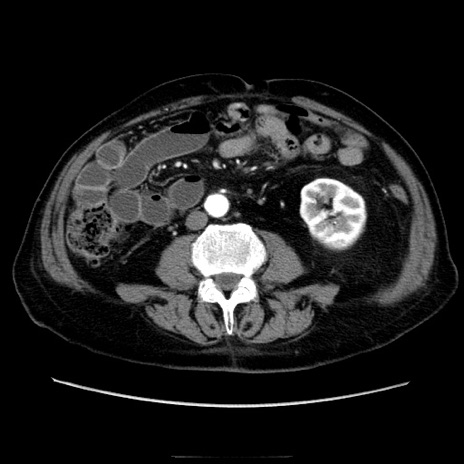

症例21(横断像)

【症例】70歳代男性

【主訴】腹痛

【現病歴】肝硬変・肝細胞癌にてかかりつけの方。約9時間前に食後より腹痛出現。症状が徐々に増悪し、嘔吐出現したため来院。

【既往歴】肝硬変、肝細胞癌(RFA、TACE後)

【身体所見】意識清明、表情苦悶様、BT 36℃、BP 129/78mmHg、P 88bpm、SpO2 97%(RA)、右上腹部から心窩部にかけて圧痛あり、反跳痛なし、筋性防御あり。

【データ】WBC 5800、CRP 0.16